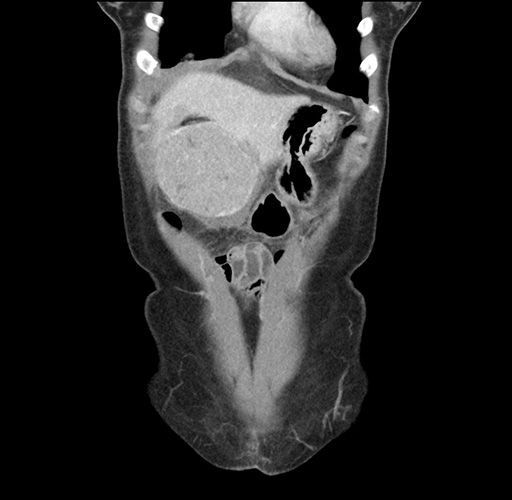

Imaging Analysis

Look through the patient's CT scan to identify any areas of concern for the necessary procedure.

Based on your CT findings, which issue(s) would give reason for "planned slowing down moment(s)" in this case?

Considering a standard left lateral sectionectomy procedure, what step(s) of the operation would you do differently in this case ?